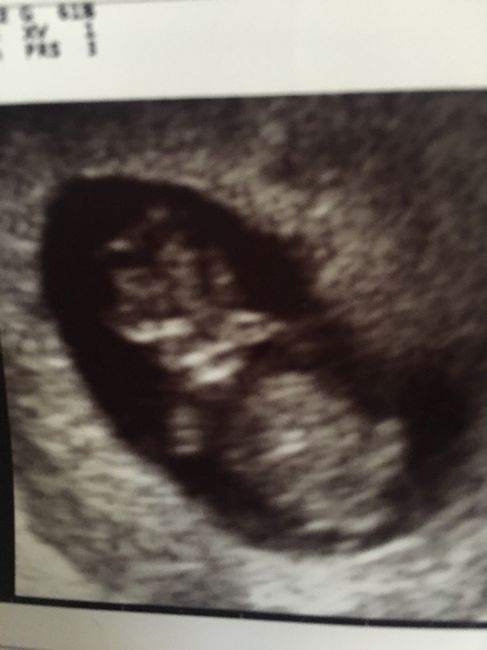

Ragazze buongiorno!Vi presento il nostro orsacchiotto! Mercoledì ho fatto la seconda visita e per fortuna sta procedendo tutto bene! Abbiamo sentito il battito e vederlo che si agitava mi ha fatto commuovere come una bambina! Sembrava come se volesse...